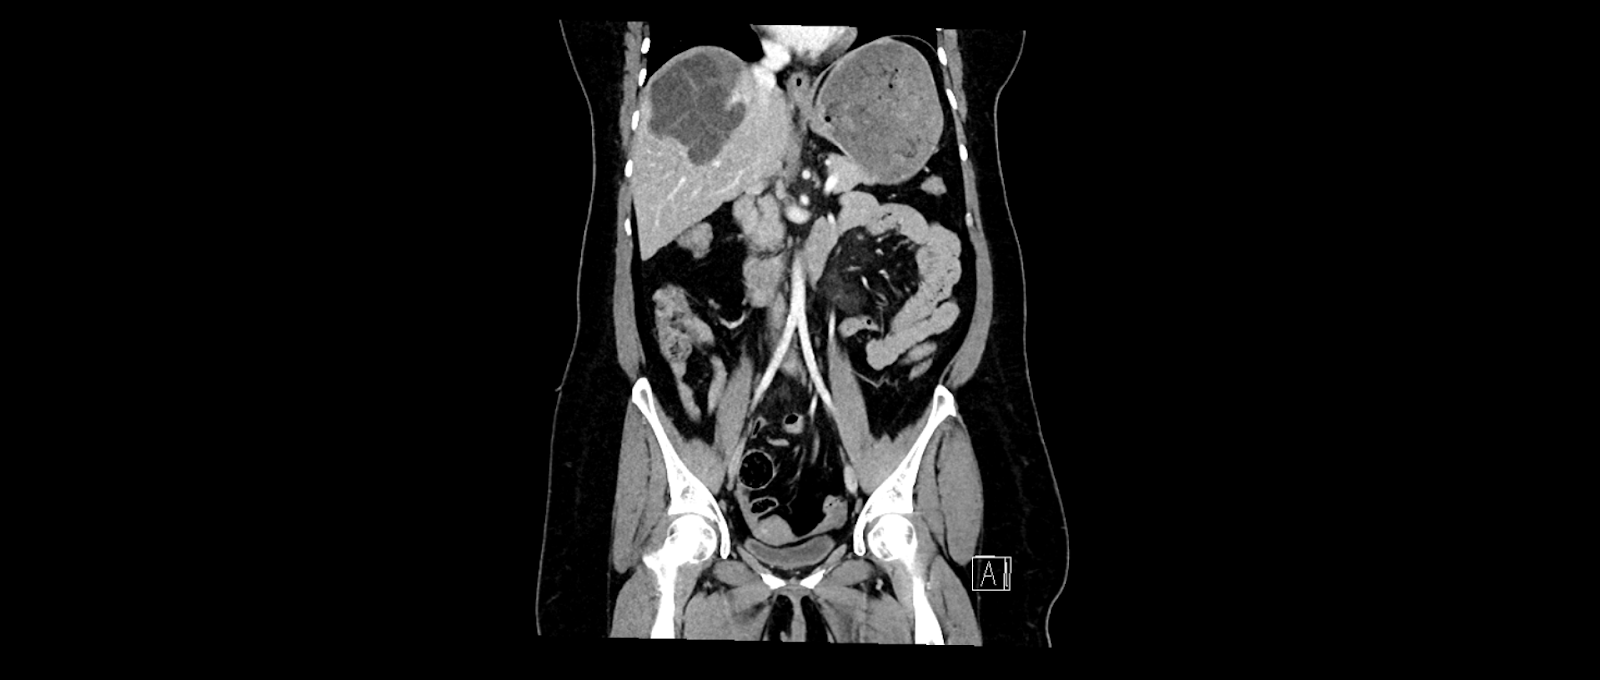

In der klinischen Untersuchung zeigt sich ein diskreter Sklerenikterus und ein leichter rechtsseitiger Oberbauchschmerz. Laborchemisch zeigen sich erhöhte Transaminasen sowie eine Bilirubinämie. Die Leukozyten und das C-reaktive Protein waren ebenfalls erhöht. In der orientierenden Sonographie bei dem Internisten zeigte sich eine ca. 16 cm messende echoarme, septierte Raumforderung, woraufhin die Patientin zur stationären Abklärung eingewiesen wurde. Bei der Aufnahme wurde eine Computertomographie des Abdomens durchgeführt.

In der CT-Untersuchung zeigte sich eine 16 x 14 cm messende, multilobulierte hypodense Raumforderung in den Lebersegmenten VII, VIII und VIa mit konsekutiver Cholestase im rechten Leberlappen. Die Pfortader und die Lebervenen waren offen. Die restlichen Organe waren unauffällig. Bei komplizierten Leberzysten wurde die Serologie für Echinokokkose abgenommen. Auf die gezielte Frage nach Kontakt zu Hunden und Füchsen hat Frau K. angegeben, dass sie drei Hunde auf dem Bauernhof hat. Der Echinokokken-IgG-Screening-ELISA war mit 47 U/ml positiv. Somit wurde die Diagnose einer Echinokokkose gestellt.